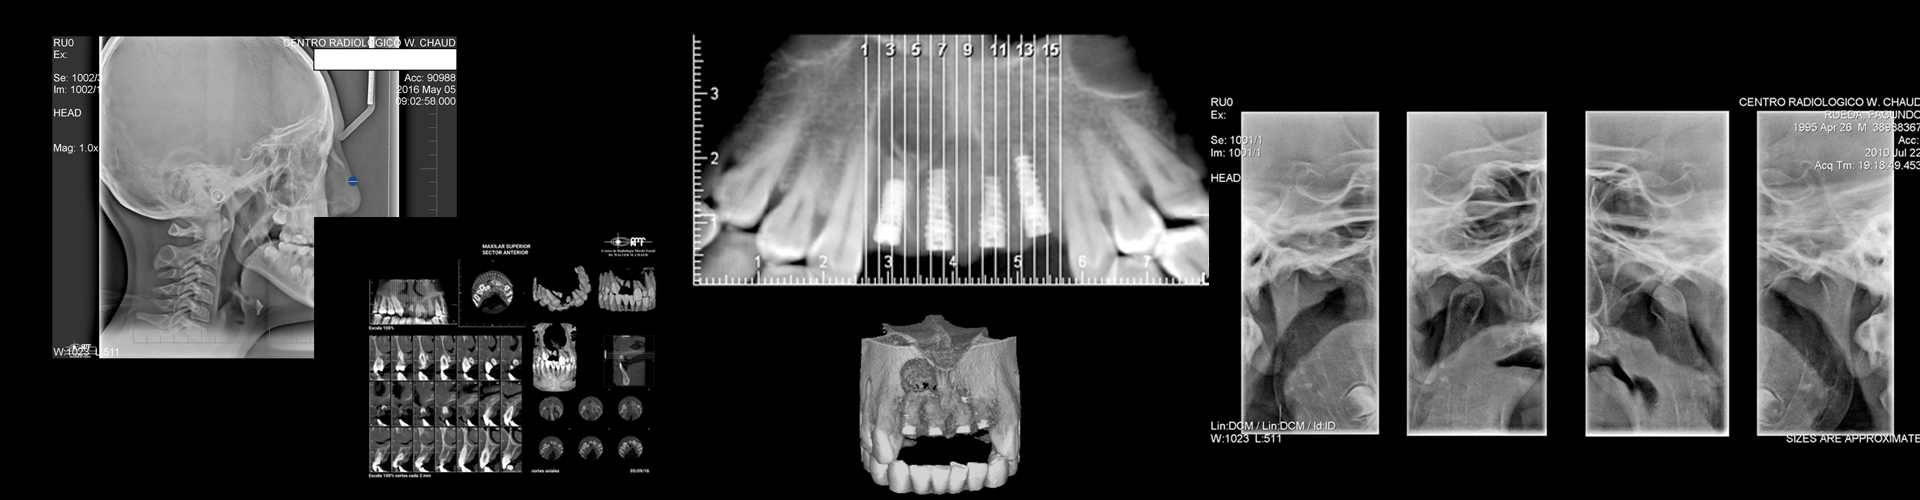

Se dedica con exclusividad a la RADIOLOGÍA ODONTOLÓGICA desde el año 1986. Lleva el nombre de quien fuera su fundador, y es administrado desde sus orígenes y hasta el presente por la Sra. Carmen H. Haack , bajo la dirección, desde el año 1.997, del Odontólogo Dr. Germán A. Villani y la colaboración desde 1.998 de la Od Martinez Maria Isabel.

Todas las radiografias se entregan impresas en películas.